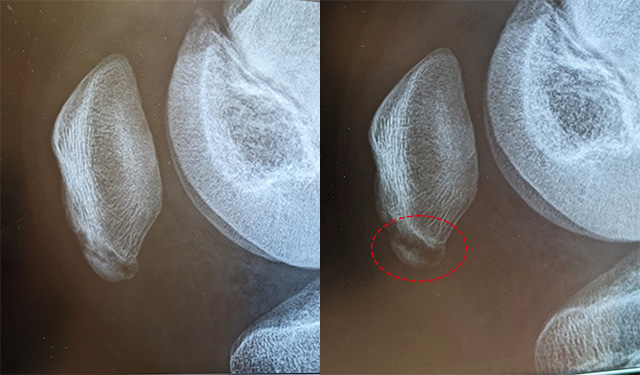

ただ、しばらくしてもなかなか練習時の痛みが良くならない……。日常生活に支障がないとはいえ、練習の度に痛がるのはおかしいと思い、病院を受診してみることにしました。出された診断結果は、『右膝蓋骨下端裂離骨折』。4週間の練習休みと安静に務めるようにと担当医の先生から言われました。